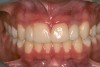

Fig 4 and Fig 5. The fused tooth was carved to resemble two teeth, matching the width of the created tooth central to tooth No. 9.

Using the wax-up as a guide, a composite restoration was fabricated for fused teeth Nos. 7 and 8 by roughening the affected area without pulpal exposure, etching the enamel, and applying primer and adhesive. Composite shade A1 was bonded to the mesial and distal surfaces, with gingival dark composite applied to the cervical “interproximal” region. The tooth was then carved to resemble two teeth, matching the width of the created tooth central to tooth No. 9 (Figure 4 and Figure 5). The patient and her family were very pleased with the result, and no postoperative sensitivity was reported.